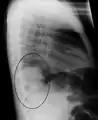

Right lower lobe pneumonia as seen on a lateral CXR